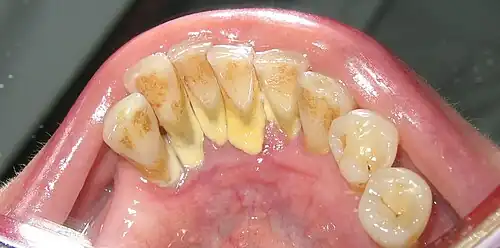

Dental Diseases

Taphonomic alterations seldom affect the teeth in the archaeological record because teeth have a high inorganic content, hence, they provide permanent records of a range of diseases. Periodontal disease, carious lesions, periapical cavities, dental calculus, intense dental wear, and ante-mortem tooth loss (AMTL) are dental conditions that are systematically recorded and studied in archaeological skeletal assemblages.[27][28] Dental diseases are especially relevant because they can provide indirect evidence of a person’s type of diet during life.[29] Furthermore, examination of the angle of tooth wear visible on the tooth crown may help differentiate dietary shifts between human populations (e.g. distinguishing hunter-gatherers and later agriculturalists).[30]

Greg Nelson and John Lukacs from the University of Oregon and Paul Yule from the Ruprecht-Karls Universität-Heidelberg in Germany analyzed AMTL, dental caries, and dental attrition in thirty-seven individuals dating to the late Iron Age in the Sultanate of Oman (100 c. BCE – 300 CE). The dental caries frequency was 35.5% and it seems that the caries onset in permanent molars began soon after eruption. AMTL occurred in 100% of preserved mandibles with frequent complete alveolar remodeling. The authors attribute the patterns observed in diets high in fermentable carbohydrates, known to be highly cariogenic (e.g. dates).[31]